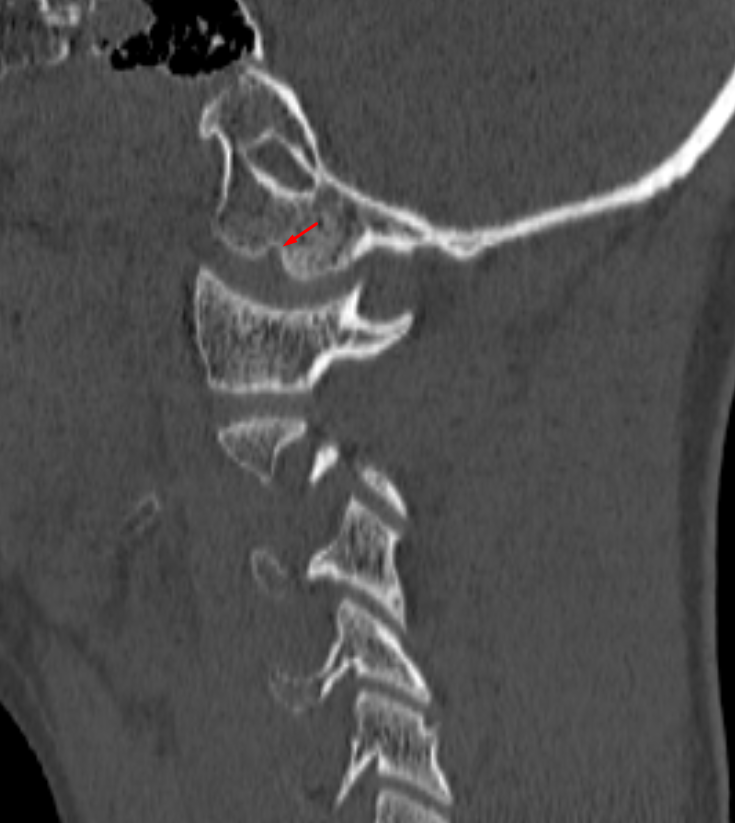

Age: 8

Sex: Male

Indication: MVC